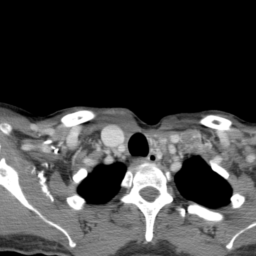

![]() |

| (a) | (b) | (c) | (d) |

Unsupervised Categorization: Our category discovery clusters are generally visually coherent within the cluster and size-balanced across clusters. However, image clusters formed only based on text information (of radiology reports) are highly unbalanced [49], with three clusters inhabiting the majority of images. Note that our method imposes no explicit constraint on the number of instances per cluster. Fig. 6 shows sample images and their top-10 associated key words from two randomly selected clusters (more results are provided in the supplementary material). The LDPO clusters are found to be clinically or semantically related to the corresponding key words, which describe presented anatomies, pathologies (e.g., adenopathy, mass), their associated attributes (e.g., bulky, frontal) and imaging protocols or properties.

The category discovery clusters employing our LDPO method are found to be more visually coherent and cluster-wise balanced in comparison to the results in [49] where clusters are formed only from text information ( radiology reports). Fig. 7 Left shows the image numbers for each cluster from the AlexNet-FC7-Topic setting. The numbers are uniformly distributed with a mean of 778 and standard deviation of 52. Fig. 7 Right illustrates the relation of clustering results derived from image cues or text reports [49]. Note that there is no instance-balance-per-cluster constraints in the LDPO clustering. The clusters in [49] are highly uneven: 3 clusters inhabit the majority of images. Fig. 6 shows sample images and top-10 associated key words from 5 randomly selected clusters (more results in the supplementary material). The LDPO clusters are found to be semantically or clinically related to the corresponding key words, containing the information of (likely appeared) anatomies, pathologies (e.g., adenopathy, mass), their attributes (e.g., bulky, frontal) and imaging protocols or properties.